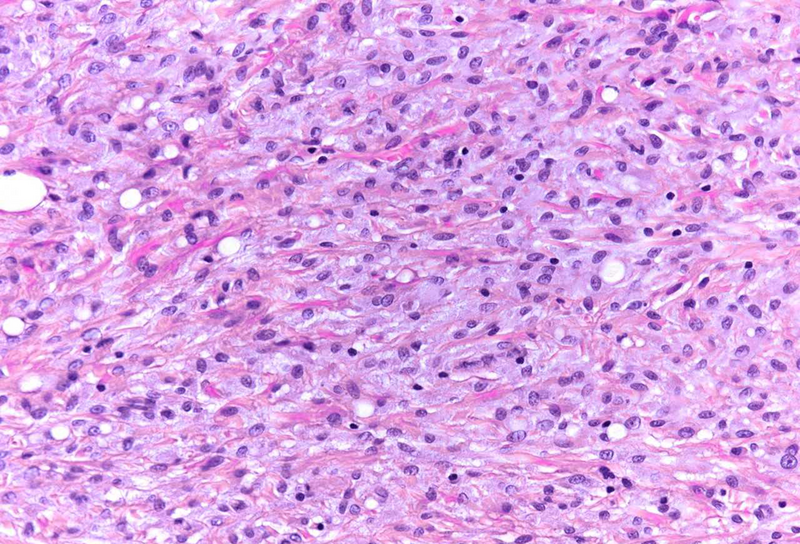

The resection specimen contained superficial remnants of the previously excised tubular adenoma (not shown). Close to the neoplastic glands, however within the submucosa, nodular aggregates of histiocytes were found (Panel A), that included vacuoles of varying size; these vacuoles were mainly empty, except for few tiny droplets of pale fluid or substance (Panels B and C). A CD68 immunostain confirmed histiocytic cell origin (Panel D). Pankeratin staining was negative within the lesion. No atypia was observed, and no eosinophils were present. The histological findings in combination with a history of polypectomy at the same site were consistent with the diagnosis of a “lifting agent granuloma”.